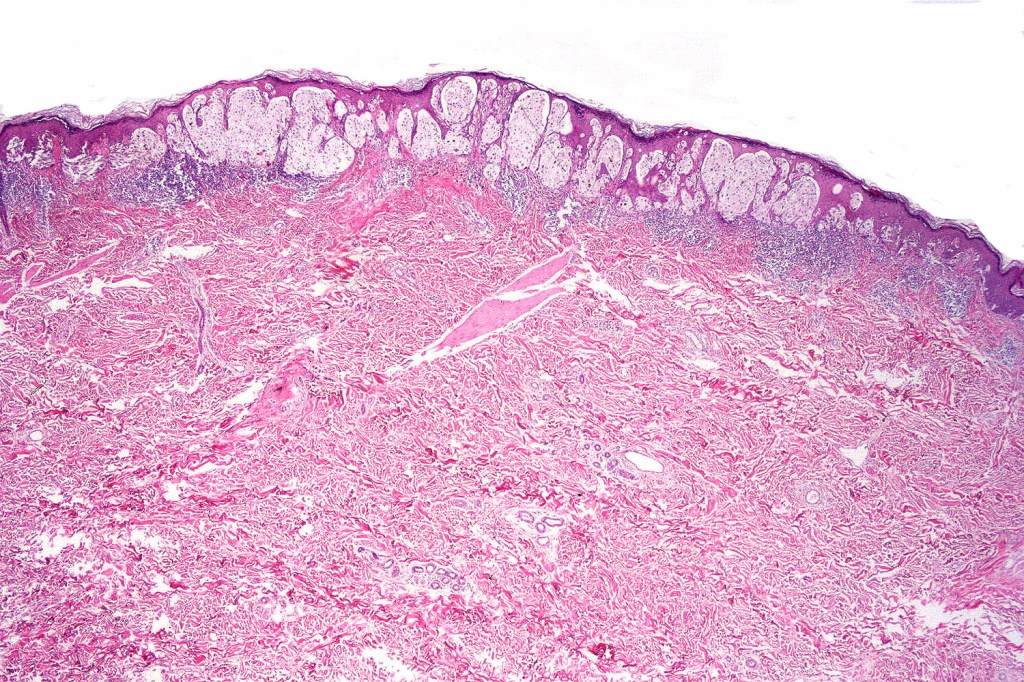

Histological features

•May affect the tumor in part or whole

•Enlarged cells with copious eosinophilic, foamy or clear cytoplasm (some authors include melanoma with clear cell change in the same category)

•Variable pigmentation

•Nuclei vesicular or hyperchromatic

•Pleomorphism is not generally marked and indeed can be very subtle

•Variable mitotic activity